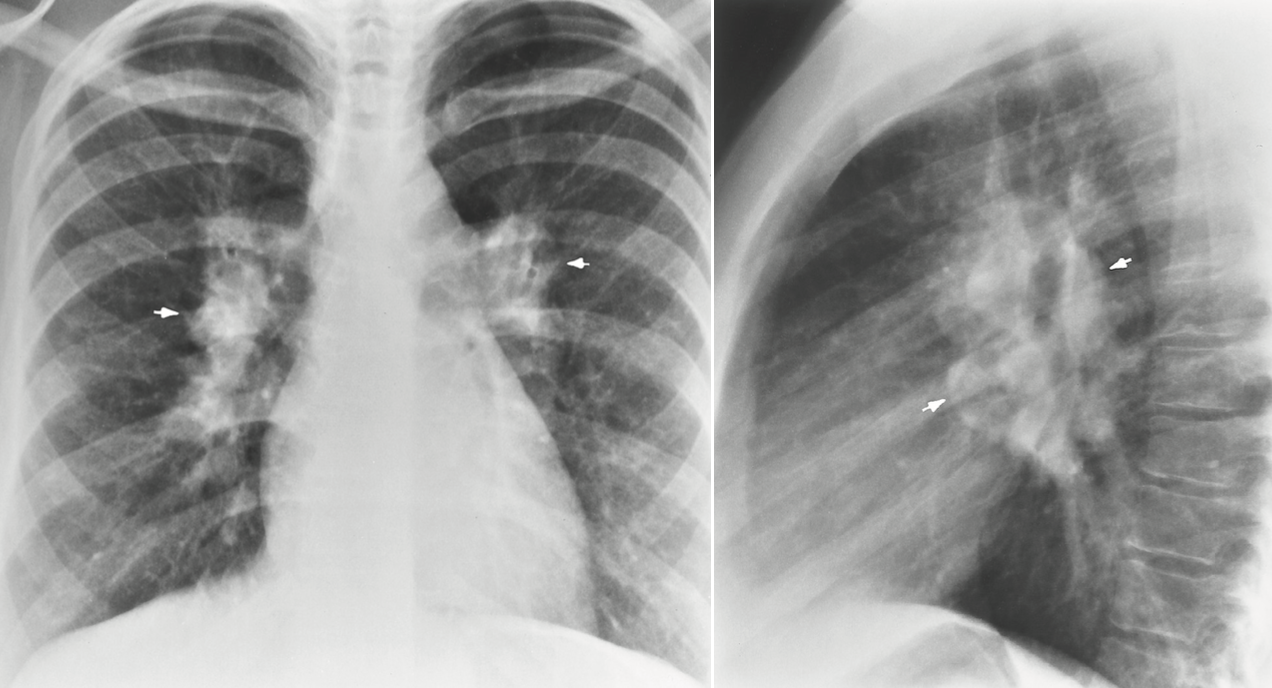

lymphoma

cancer of lymphatic system when affected cells are produced at high rate

hodgkin

non-hodgkin

2 classifications of lymphoma

Mediastinal lymph node enlargement

is the most common radiographic finding in lymphoma

40% happens in parenchymal organs (lymphoma) outside of lymph that is more severe at any age

90% originate in lymph nodes